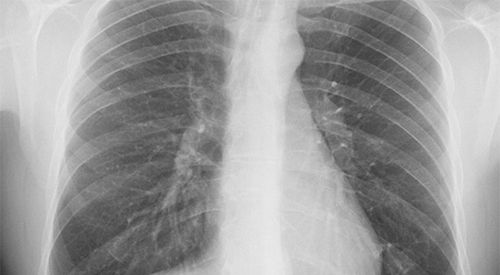

- Radiografía de tórax o tomografía pueden mostrar datos de consolidación o derrame pleural.